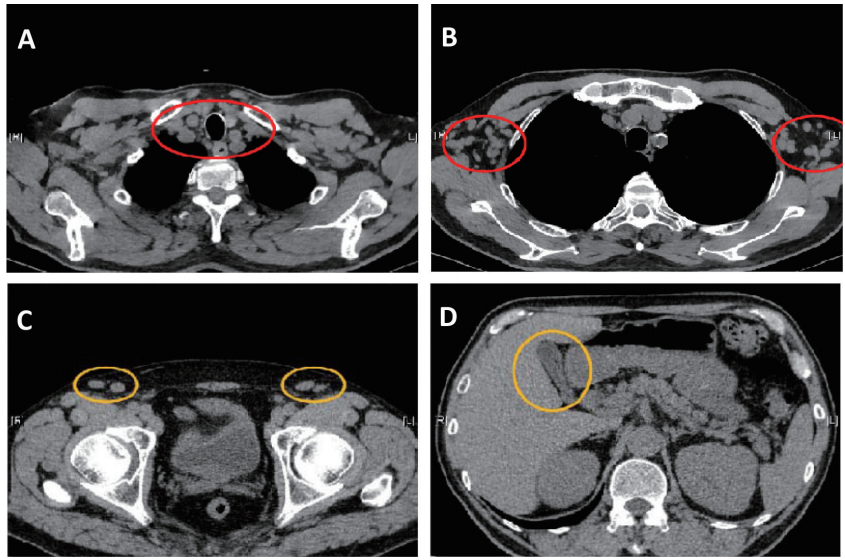

CT 头颅双侧侧脑室旁缺血灶;脑萎缩。胸腹部:左肺上叶、右肺上叶小结节伴钙化,纵隔、腋窝、腹股沟淋巴结肿大,轻度脂肪肝、肝内多发囊肿,胆囊壁稍增厚(图1)。

图1 胸腹部CT(2019年7月30日)

图1A 纵隔淋巴结肿大;图1B 腋窝淋巴结肿大;图1C 腹股沟淋巴结肿大 ;图1D 胆囊壁增厚